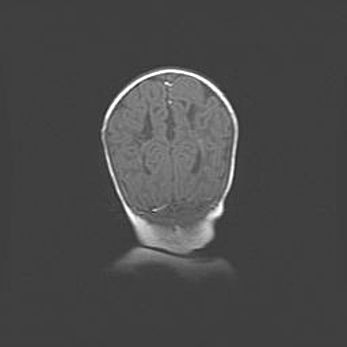

Церебральная ишемия II.

Возраст: 5 дней

Вес: 3400 г

Пол: женский

Окружность головы: 35 см

Срок гестации: 39 недель

Церебральная ишемия – это заболевание, характеризующееся недостаточностью (гипоксией) либо полным прекращением (аноксией) снабжения мозга кислородом по причине закупорки одного или нескольких сосудов. Это приводит к  что метаболическим расстройствам различной степени тяжести в тканях головного мозга, развитию коагуляционных некрозов и гибели нейронов.